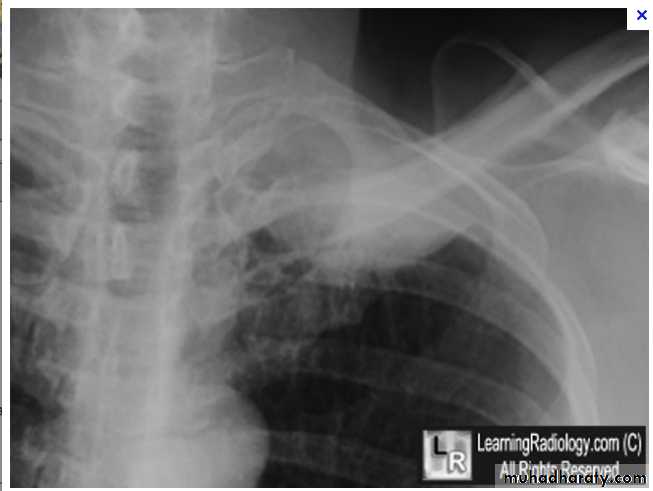

Tension Pneumothorax. Portable chest film in a 43-year-old woman with ARDS shows a large right pneumothorax with mediastinal shift and ipsilateral diaphragmatic depression, suggesting tension.

Air was evacuated under pressure during emergent placement of a right chest tube.